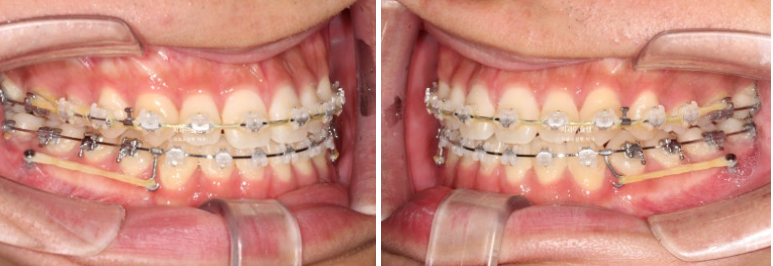

이제 전후 비교 보겠습니다.

치료 도중 군입대를 하면서 치료가 지연되어 토탈 기간은 2년 6개월 걸렸습니다.

23.06~26.01